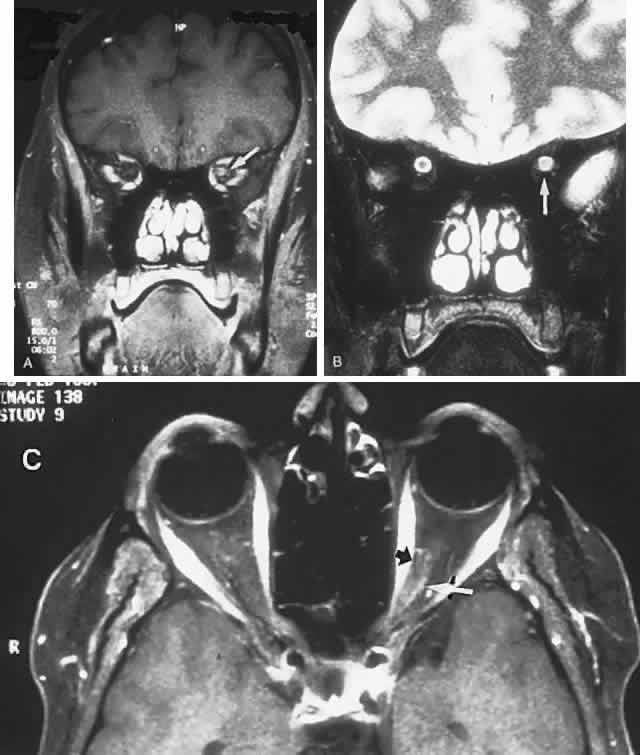

In contrast to transient symptoms and signs of retinal microembolic episodes, a condition of chronic ocular hypoxia (ocular ischemic syndrome) occurs less frequently, resulting from diffuse vascular occlusive disease of the aortic arch or common carotid artery. Acute or chronic occlusion with insufficient collateralization produces an ischemic pseudo-inflammatory uveitis, which variably includes an injected painful globe, corneal edema, aqueous flare and cells, a mid-dilated fixed pupil, rubeosis and iris atrophy, rapidly advancing cataract, either hypotony or elevated intraocular pressure (“neovascular glaucoma”), retinal microaneurysms and new vessel formation, posterior pole and mid-peripheral blot hemorrhages, macular edema, venous dilation and “sausaging,” cytoid infarcts (cotton-wool spots) of the nerve fiber layer, and arterial occlusions (Fig. 7; see Table 4). The hypoxemic fundus changes constitute a picture of venous stasis (low-pressure) retinopathy, perhaps the commonest ocular sign of chronic carotid obstruction.

Fig. 7. Ocular hypoxia with subacute carotid occlusion. The patient complained of a painful red eye. A. Anterior segment shows an irregular, fixed pupil and iris rubeosis (arrows). B. Fundus demonstrates combined retinochoroidal infarction with acute excavation of the optic disc. Arteriography revealed right internal carotid occlusion.

Ischemic photoreceptor metabolism accounts for subjective afterimages following exposure to bright light, including a positive photostress test60 (see Volume 2, Chapter 2). Low retinal arterial pressure may be detected by observing pulsation or collapse of the disc arterioles with even slight fingertip pressure exerted on the globe. Such borderline perfusion associated with carotid stenosis and retinopathy may be heralded by postprandial visual loss.61 In the situation of chronic, subacute, or rapidly progressive ischemic oculopathy, giant cell arteritis must be considered in the differential diagnosis, and chronic venous obstruction or diabetic retinopathy may produce similar fundus appearance.